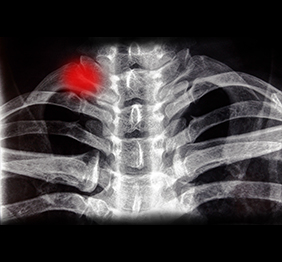

Radiografie digitala

Procedura medicala non-invaziva care permite medicilor sa investigheze o serie de afecțiuni, cu ajutorul razelor X.